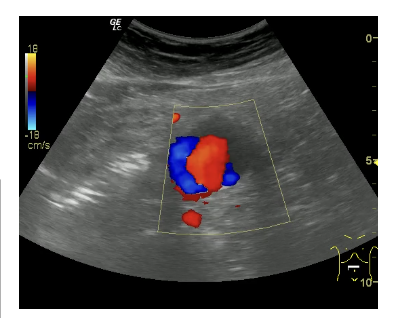

Informe: Hígado de tamaño y ecogenicidad normal. Vesícula distendida con 2 litiasis de 2 x 3 mm en su interior. Páncreas y bazo de ecoestructura normal. Ambos riñones de tamaño, ecogenicidad en rango, diferenciación corticosinusal. Vena porta, cava inferior y aorta en el área del lóbulo hepático izquierdo de calibre normal. Aneurisma de aorta abdominal descendente hasta su bifurcación de ambas iliacas de 3.29 cm en su eje trasversal con engrosamiento de pared posterior.